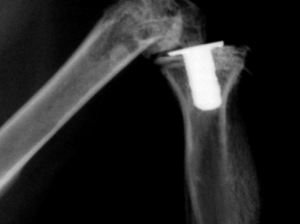

骨の1/3~1/2大の骨片に割れた時には、厳密に整復したのち、ギプス包帯で固定すると、予後が良好で、再び競走が可能なまでに回復することがあります。

圧着ネジを使用することもあります。